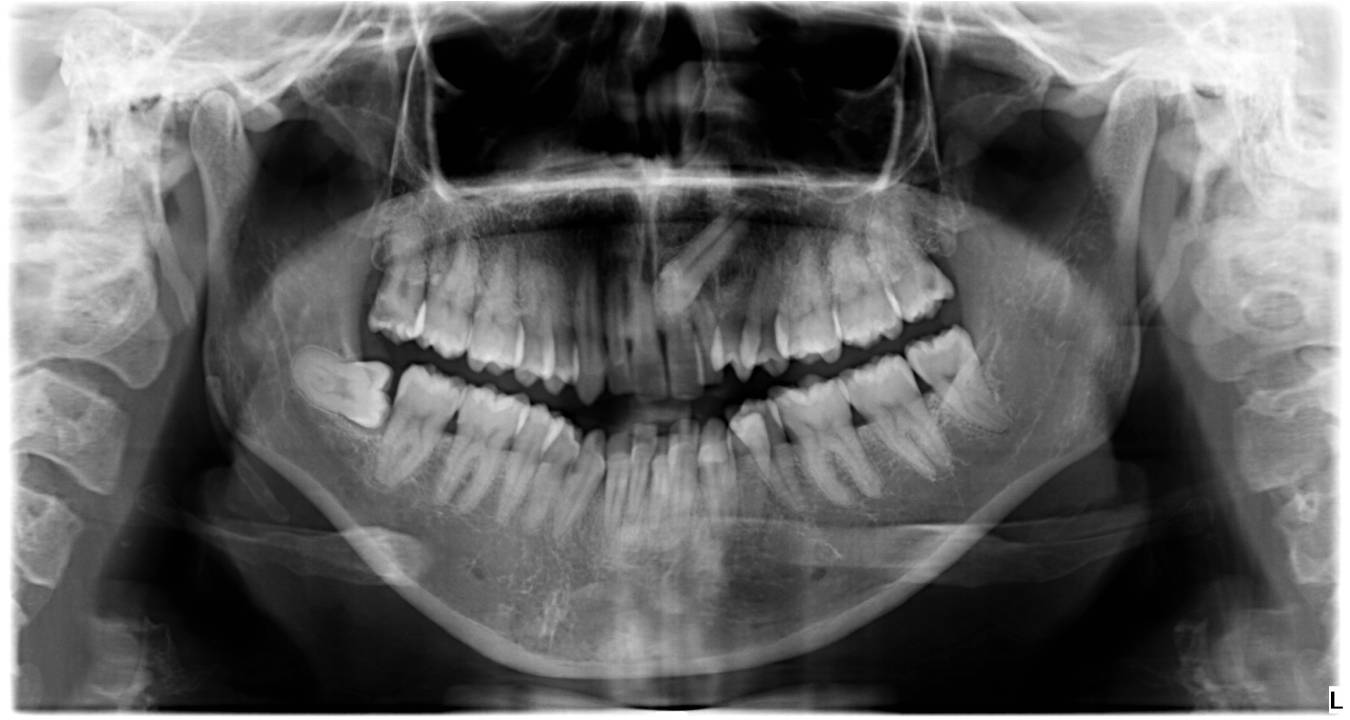

Extracción de muelas del juicio

Cuando estas muelas no tienen suficiente espacio para salir correctamente, causan infecciones repetidas, dolor, apiñamiento dental o están en mala posición, lo mejor es extraerlas. Es un procedimiento común y rápido, realizado bajo anestesia local.